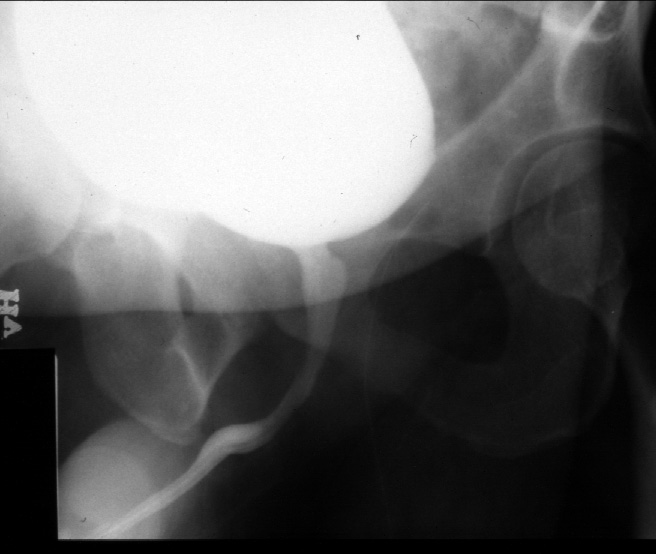

Note. Contrast has been placed within the urinary bladder via a urethral

catheter. The bladder is filled. The patient is turned slightly

to his right. The radiograph is exposed as the patient is urinating.

Identify -- bladder, prostatic urethra, bulbous urethra, penile urethra